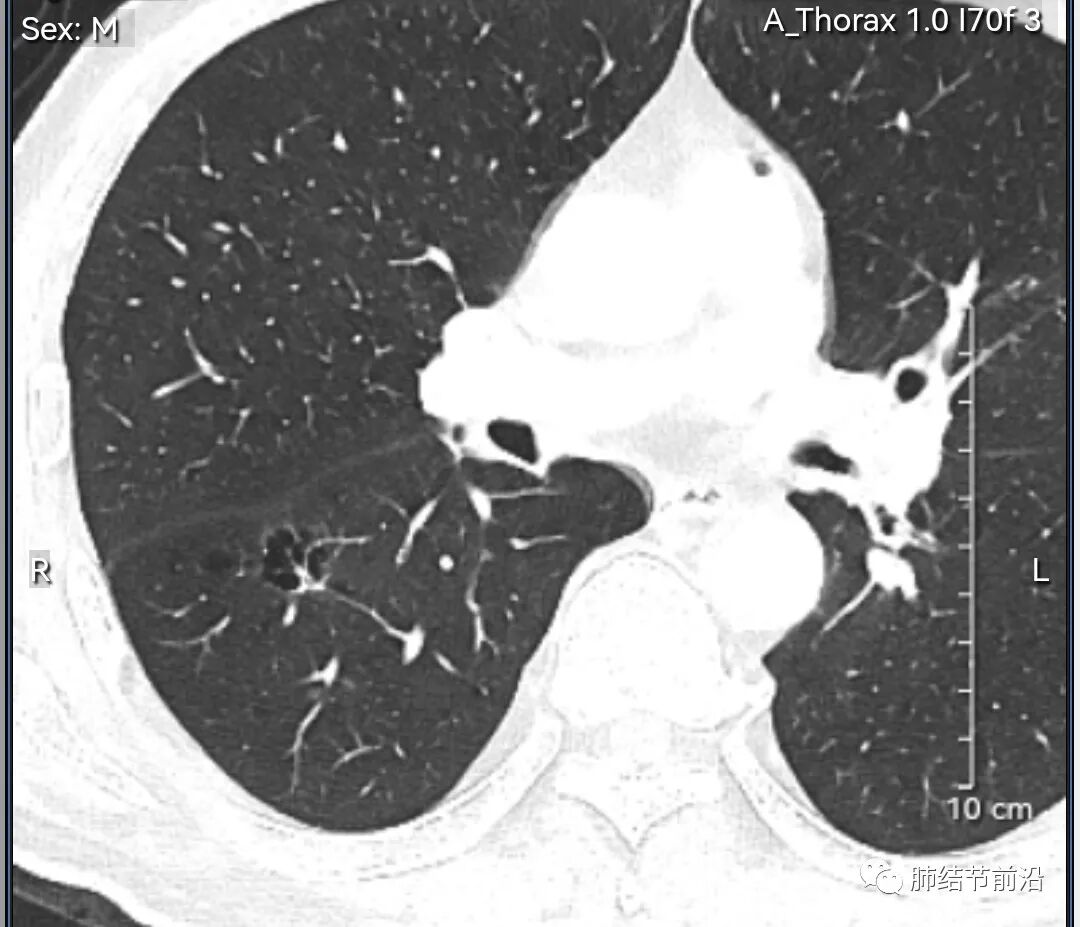

男性,67岁,重度吸烟史。CT发现右下肺囊腔。来看一下这个CT的特点:

该囊腔形态非常有特点,和常见的圆形肺大泡有很大的区别。

1.囊腔中央实性成分,周围有磨玻璃影。

2.囊腔中央有血管。

3.囊腔外周有分叶形态。

4.囊腔有胸膜牵拉。

出现这几种形态,CT可以确认恶性的腺癌。这个囊腔形成的机制,为肿瘤实性成分堵塞细支气管形成活瓣,肺泡内压力增高破裂行成,因此肺内血管成分保留。由于肺泡压力增高,而呈分叶状。另外,也有肿瘤的胸膜牵拉这一特点。

囊腔周围磨玻璃+囊腔中央血管为特征性表现。如果持续存在,几乎可以100%确认为早期肺腺癌。